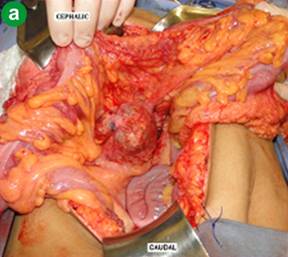

All patients in our 10-cases series underwent surgical treatment, the head of the pancreas (Table 2 and Figure 4a) and the pancreatic body (Table 2 and Figure 4b) were the usual location of the tumor. Consequently, the most common used therapeutic surgical procedures performed were: Whipple’s operation, performed for tumors in the head of the pancreas; and body-tail pancreatectomy with splenectomy, performed for tumors in the body and tail of the pancreas (Figures 2b and 5) (Table 2). It is worth emphasizing that two out of the 4 patients with tumor in the head of the pancreas; underwent Whipple’s operation along with vascular resection followed by reconstruction with splenic vein graft [15] and internal jugular vein patch (Table 2 and Figure 6). There was no death in this cohort (Table 2).

|

Figure 4. Image featuring the view of the abdominal cavity inventory showing SPN pancreatic. Pancreatic head tumor identified in the Case #8 (a.). Pancreatic body tumor (green arrow) identified in the Case #6 (b.). Pancreatic tail (yellow arrow). |